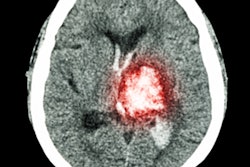

![Example of a prompt and subsequent outputs of GPT-4 that attained lower concordance (60% [3/5]) and acceptance (80% [4/5]). Image courtesy of Radiology through CC BY 4.0.](https://img.auntminnieeurope.com/files/base/smg/all/image/2023/07/ame.2023_07_06_21_31_5861_2023_07_06_ChatGPT_example.png?auto=format%2Ccompress&fit=max&q=70&w=400) Example of a prompt and subsequent outputs of GPT-4 that attained lower concordance (60% [3/5]) and acceptance (80% [4/5]). Image courtesy of Radiology through CC BY 4.0.

Example of a prompt and subsequent outputs of GPT-4 that attained lower concordance (60% [3/5]) and acceptance (80% [4/5]). Image courtesy of Radiology through CC BY 4.0.Next, three experts in each subspecialty provided their consensus of the five most important differential diagnoses for each pattern. Experts were also asked to determine the number of AI diagnoses that were "acceptable."

According to the analysis, GPT-4 attained a concordance of 68.8% (55 of 80) with the experts at determining top differential diagnoses based on imaging patterns, and 93.8% (75 of 80) of differential diagnoses proposed by GPT-4 were deemed acceptable alternatives.